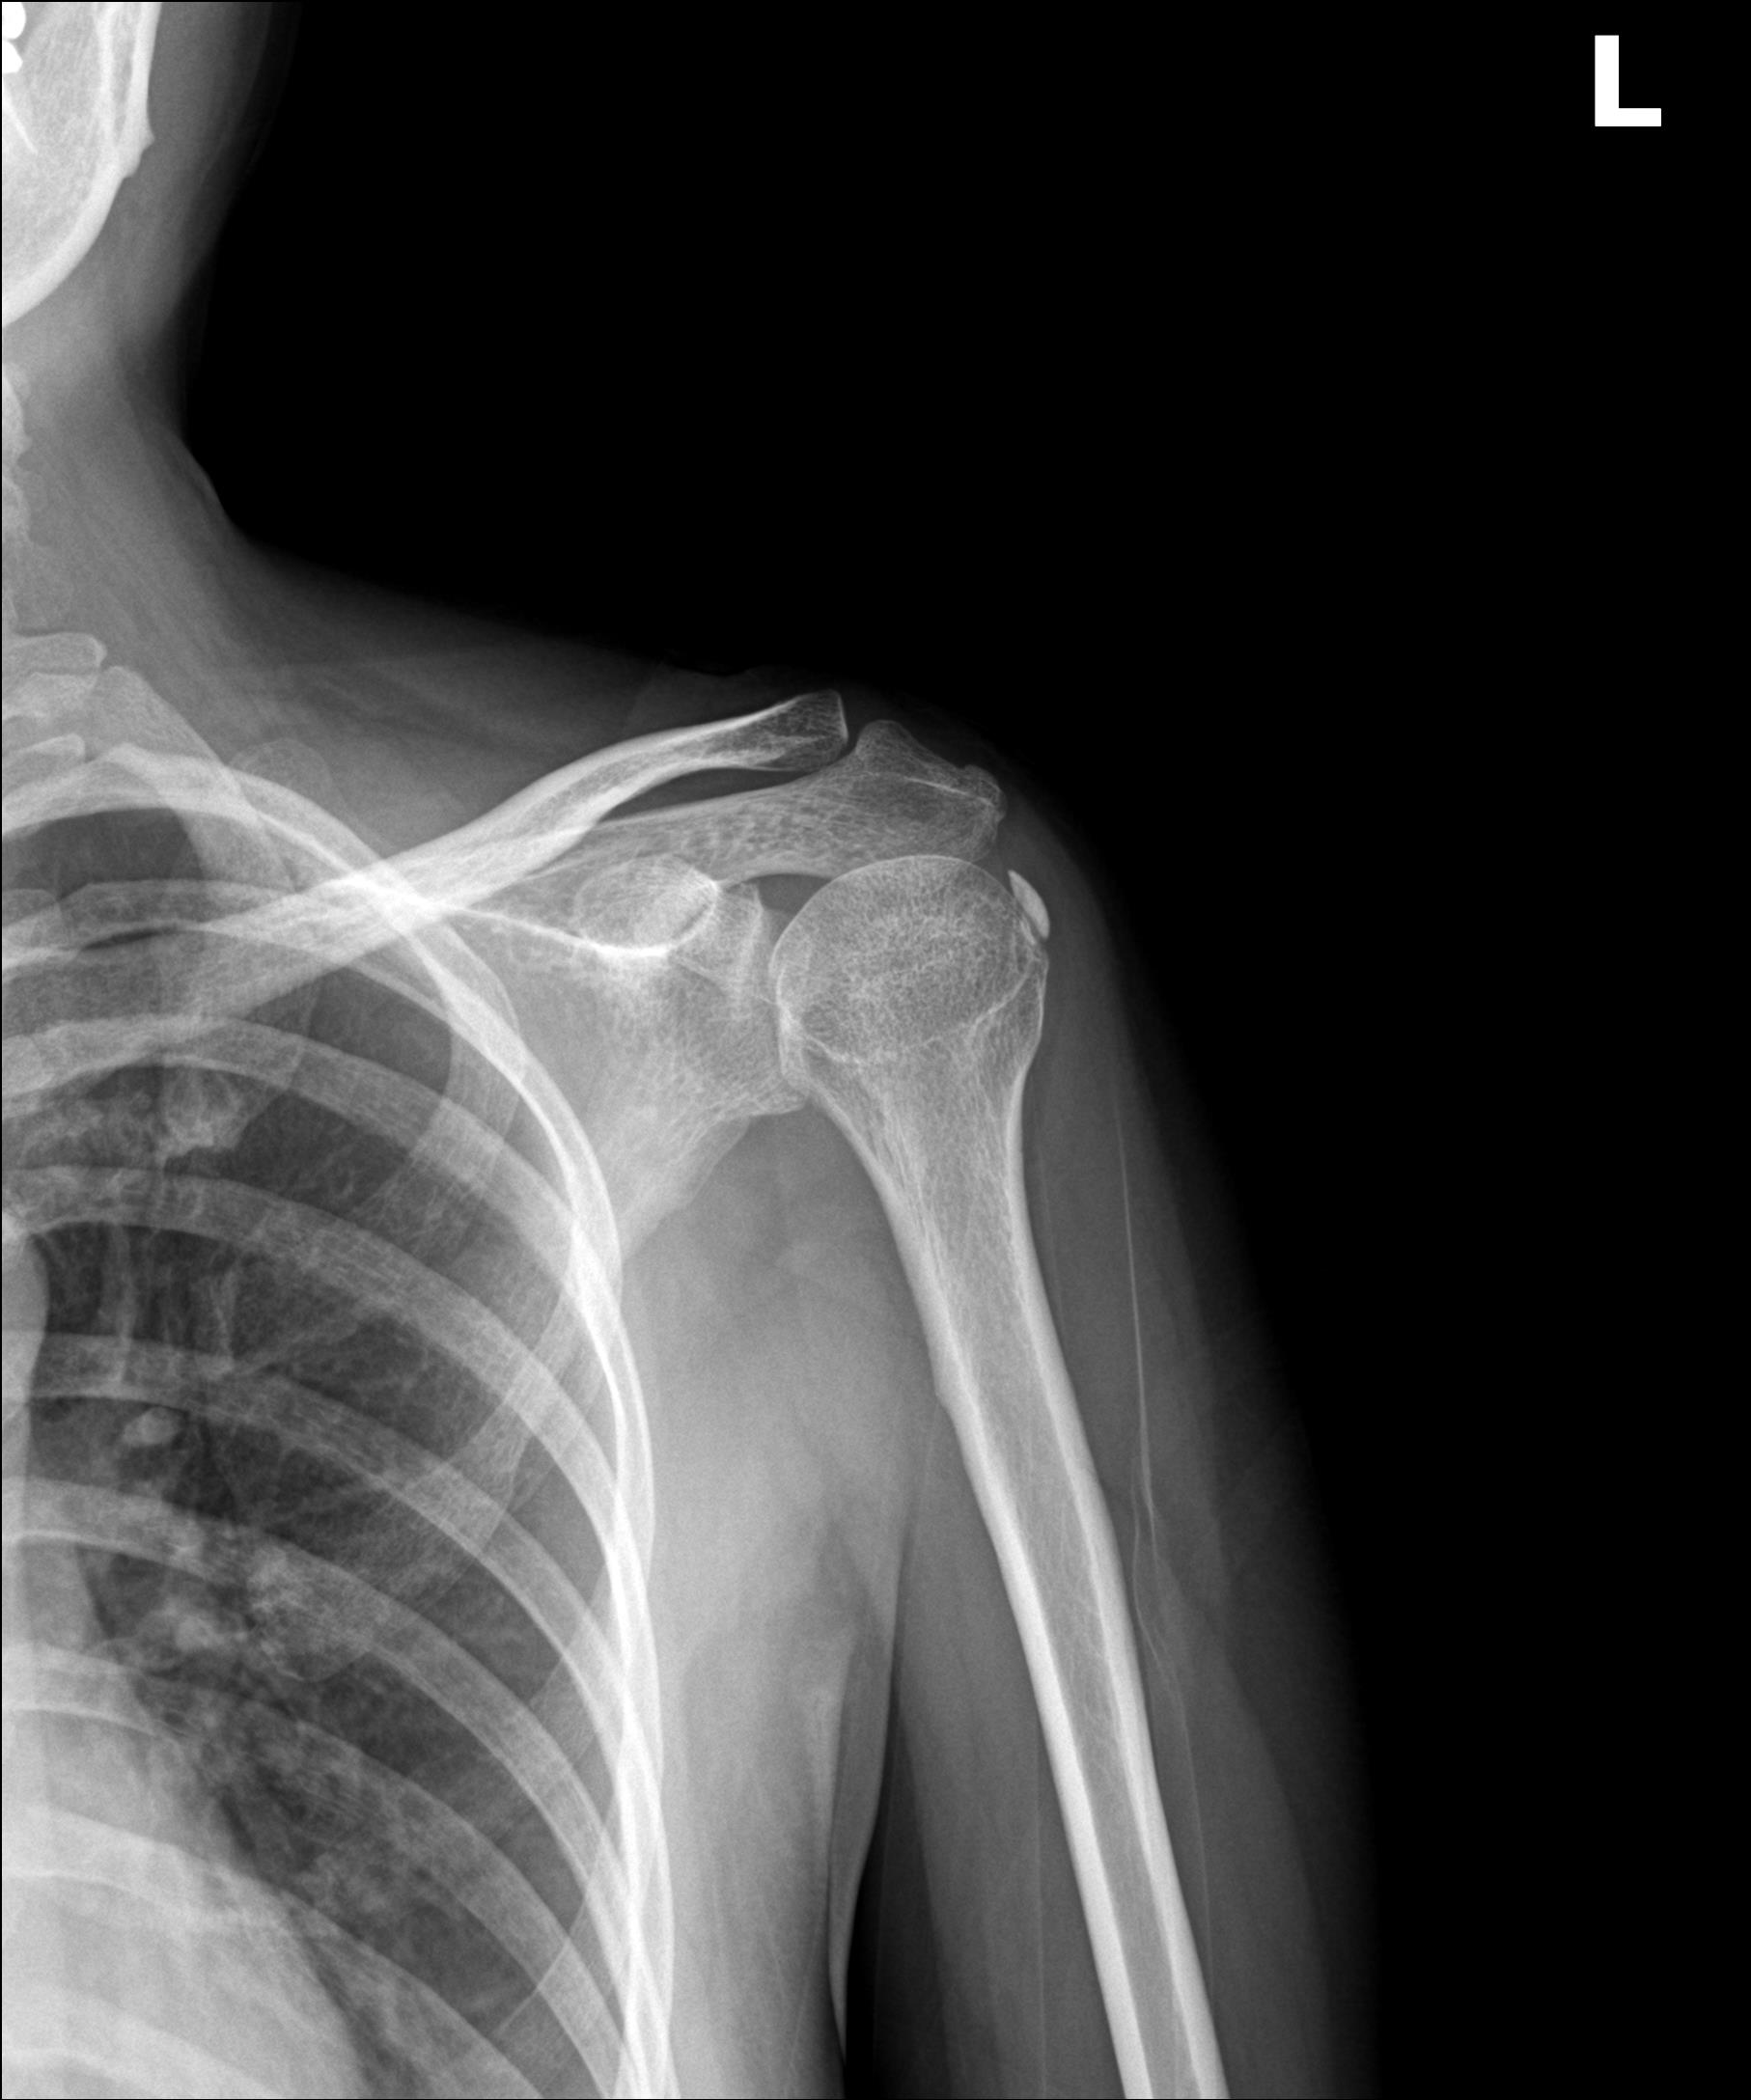

케이스 2: 휴지기 중형 석회 (1회 제거)

환자: 40대 여성, 좌측 어깨 야간통 1년

시술 전:

약 1.2cm 석회, 휴지기

충격파 10회 + 주사흡입술 2회 받았으나 호전 없음

시술 후:

1회 분쇄흡입술로 제거

야간통 소실, 수면 가능해짐